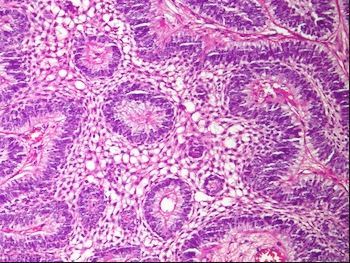

What is the triad seen in Toxoplasma lymphadenitis?

• Follicular hyperplasia

• Intrafollicular epithelioid histiocytes

• Monocytoid B-cells in sinuses (see pic)

PCR confirms